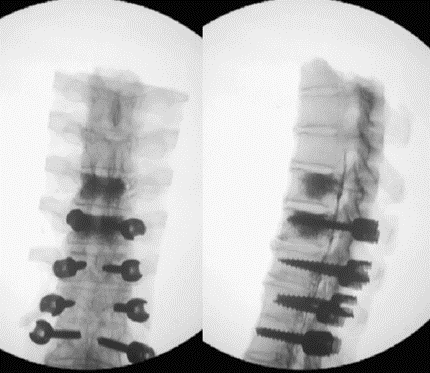

图12 CBT+TT+多棒固定

CBT+TT+多棒固定

从融合节段向活动节段未行过渡性手术,导致局部应力分布不均,局部应力过于集中,也是交界性问题的危险因素之一。

长节段固定时,融合区和活动区应适当行过渡性手术,可降低PJK发生的风险。

图13 长节段全椎弓根螺钉固定,局部应力过于集中